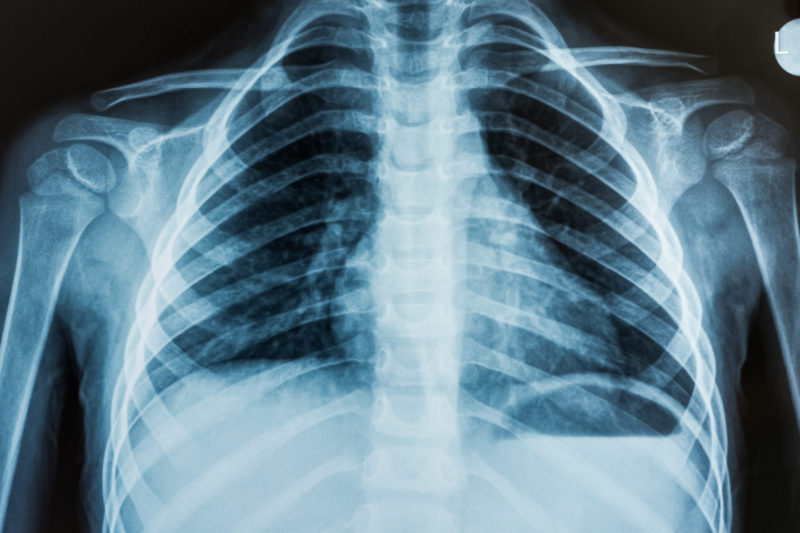

Из этого возникает третье отличие методов: контрастность МРТ очень высока в структурах, содержащих водород (то есть вода и органические молекулы, из которых состоит большинство тканей в организме), и низка в структурах, его не содержащих (например воздух в лёгких и кальций в костях). В то время как на рентгенограммах и компьютерных томограммах без дополнительного контрастирования крайне сложно различить нюансы строения мягкотканных структур, однако лёгкие и кости визуализируются отлично.

Различная область применения двух методов в современной медицине вытекает из описанных выше особенностей: рентгенография чаще используется для визуализации костных изменений (например при переломах костей) и органов, содержащих воздух — лёгкие, околоносовые пазухи, а МРТ — для визуализации мягкотканных структур (головной мозг, органы брюшной полости и таза, суставы). Таким образом, в отличие от рентгена, МРТ позволяет оценить хрящи, мениски, связки и другие мягкотканные структуры, которые в первую очередь страдают при хронических дегенеративных и травматических изменениях.